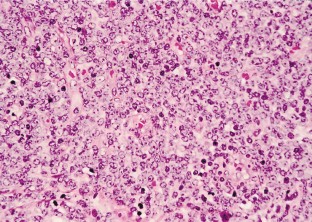

Miyazato, H., Sono, H., Naiki, Y. et al. Detection of myeloperoxidase gene expression by in situ hybridization in a case of granulocytic sarcoma associated with AML-M0. Leukemia 15, 1797–1799 (2001). https://doi.org/10.1038/sj.leu.2402270